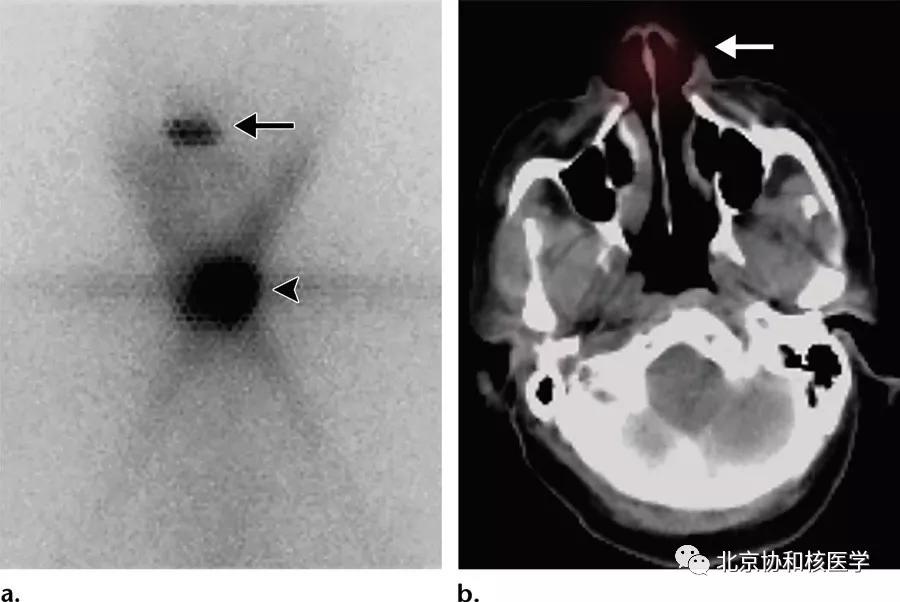

脑膜瘤所致碘摄取: